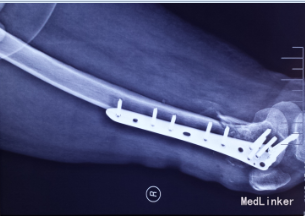

光片诊断患者骨折端粉碎,软组织损伤,发生股骨踝间骨折。采用切开复位,普通钢板、髁部支撑钢板内固定治疗股骨髁间粉碎性骨折。

股骨踝间骨折予以L型髁钢板、髁支持钢板、普通钢板加骨栓、克氏针、外固定支架固定治疗效果良好。 在恢复过程中不要吃生冷、刺激、茶叶白酒、饮料容易造成骨质疏松的食品和饮料、也不要吃猪肉等寒性食物以免影响血液循环、留下后遗症。功能锻炼越早越好。它可以促进血液循环,减少肌萎缩,消除软组织肿胀,防止骨质疏松,加快骨折愈合。